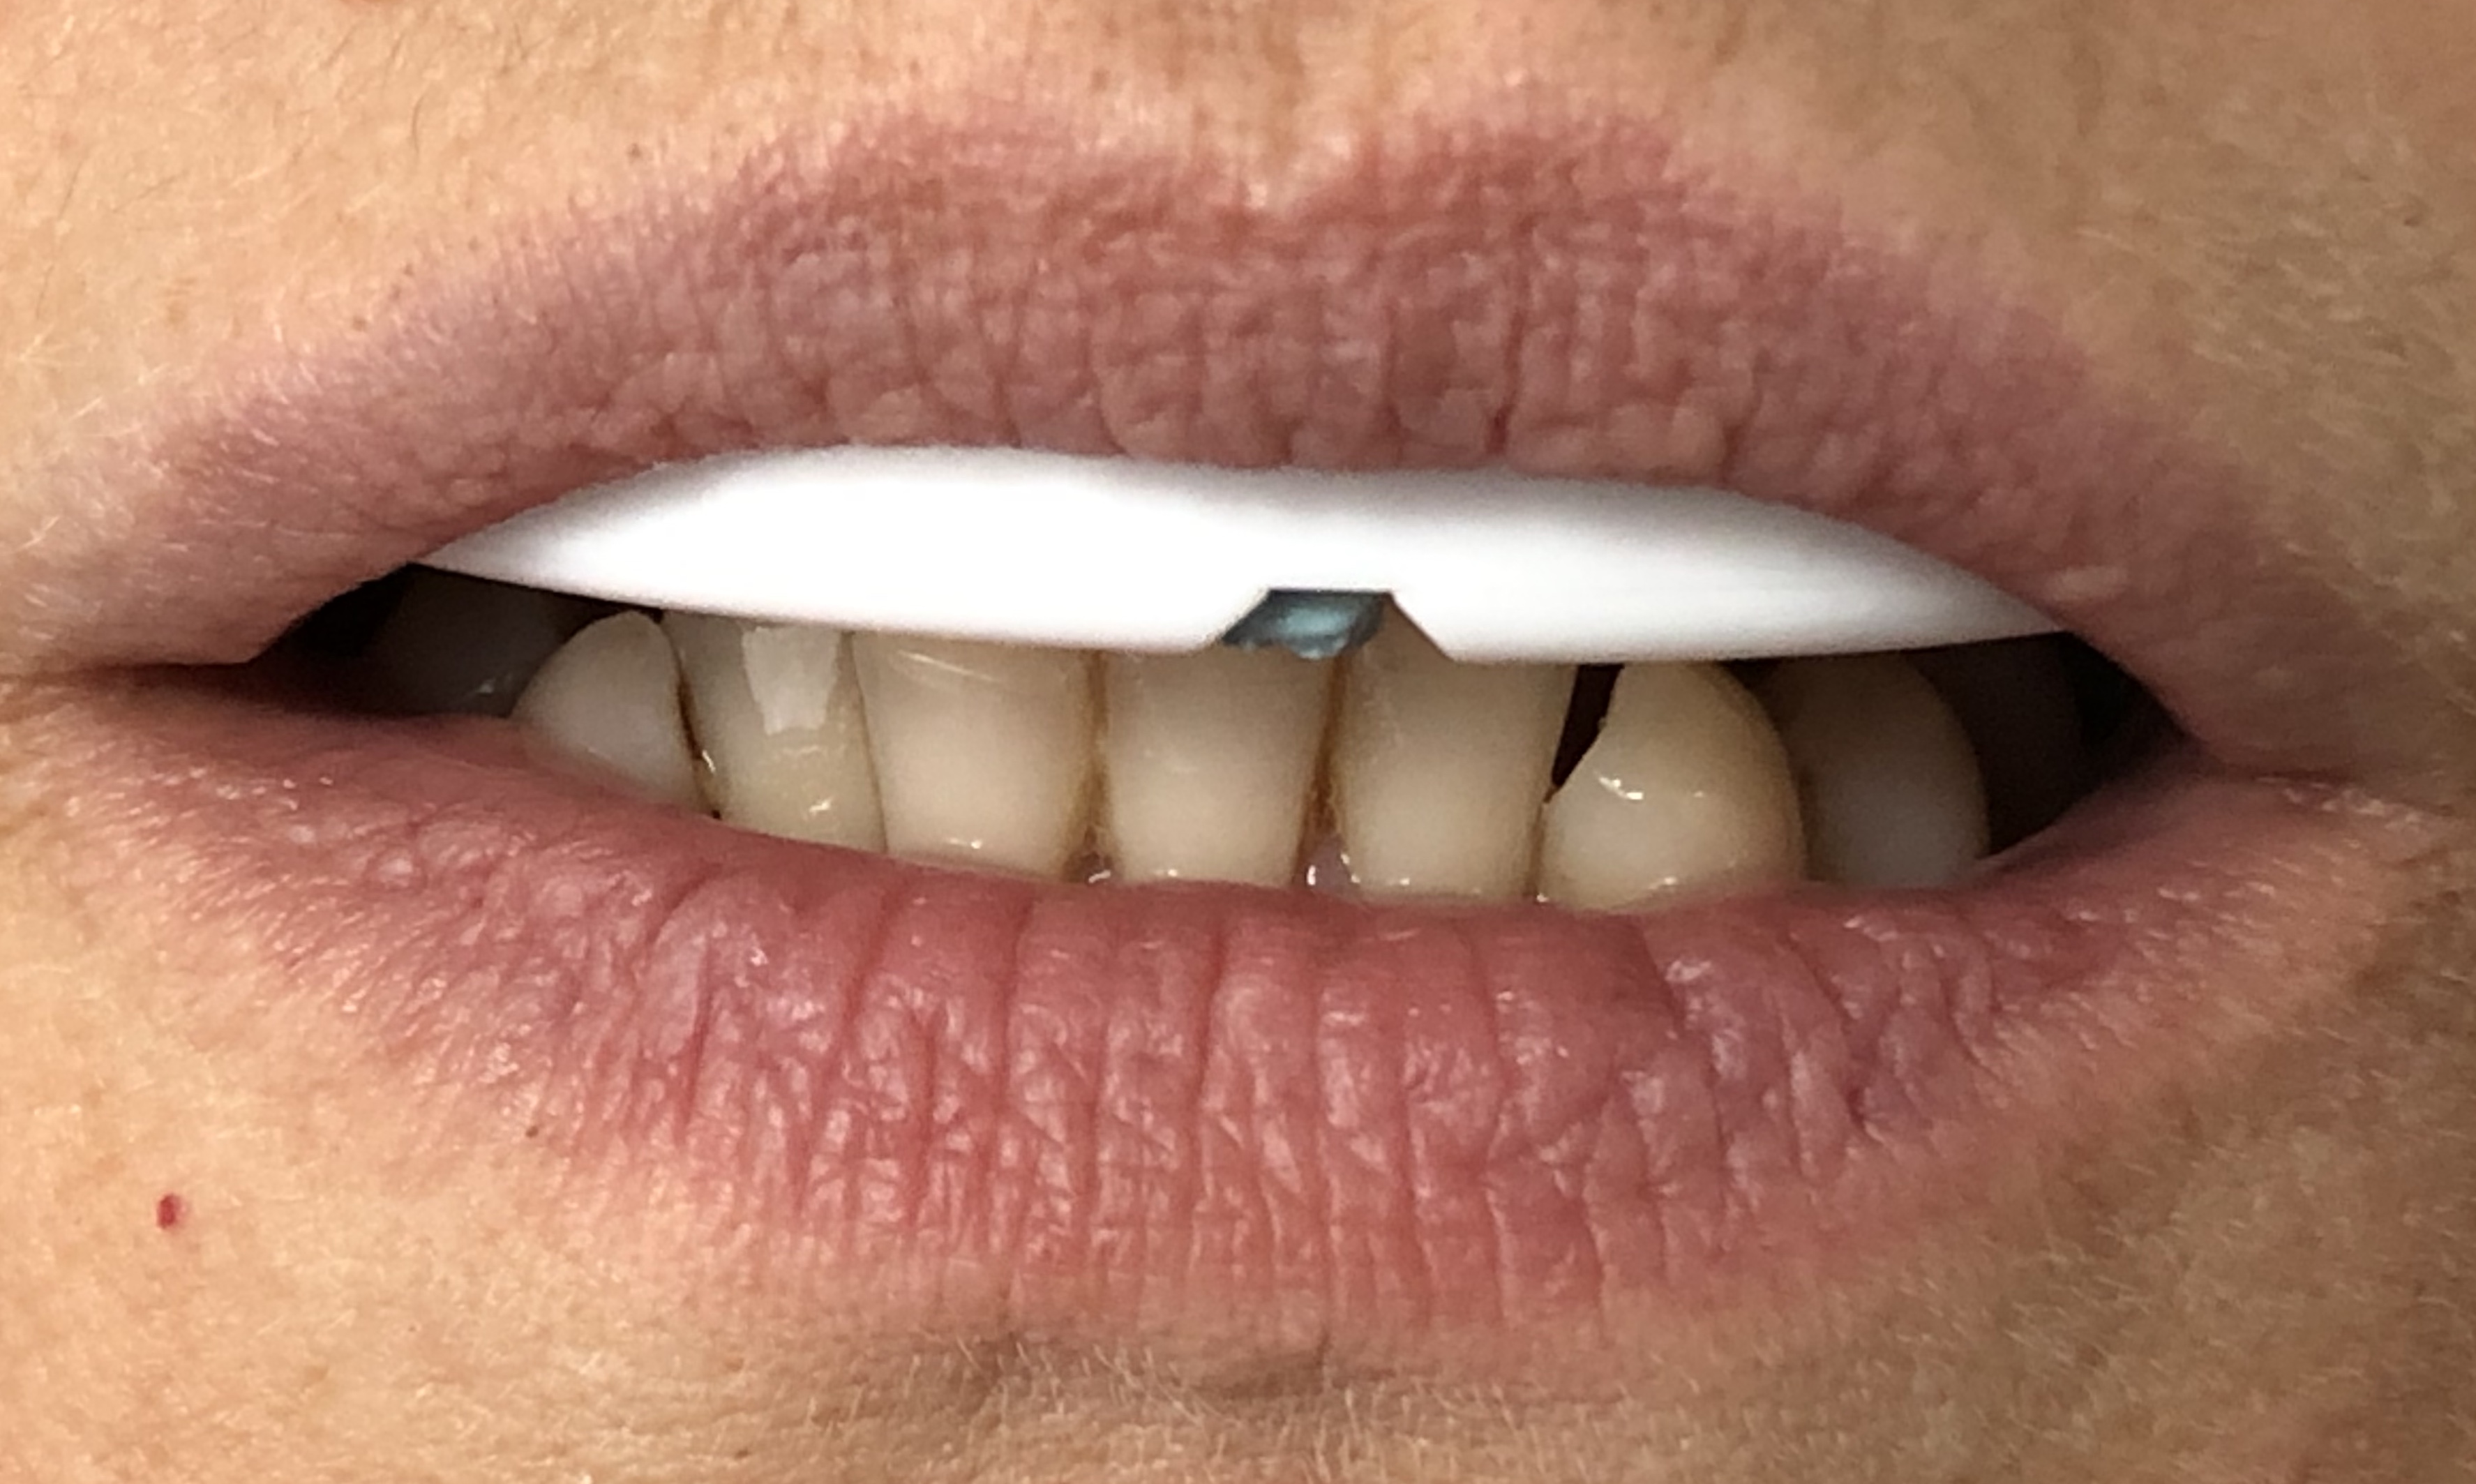

W celu relaksacji mocno napiętych mięśni żucia pacjentka otrzymała do domu szynę deprogramacyjną QuickSplint (ryc. 5, 6) do stosowania w nocy oraz w miarę możliwości w dzień – w czasie pobytu w domu.

Ryc. 5. Szyna QuickSplint.

Ryc. 6. Szyna QuickSplint.